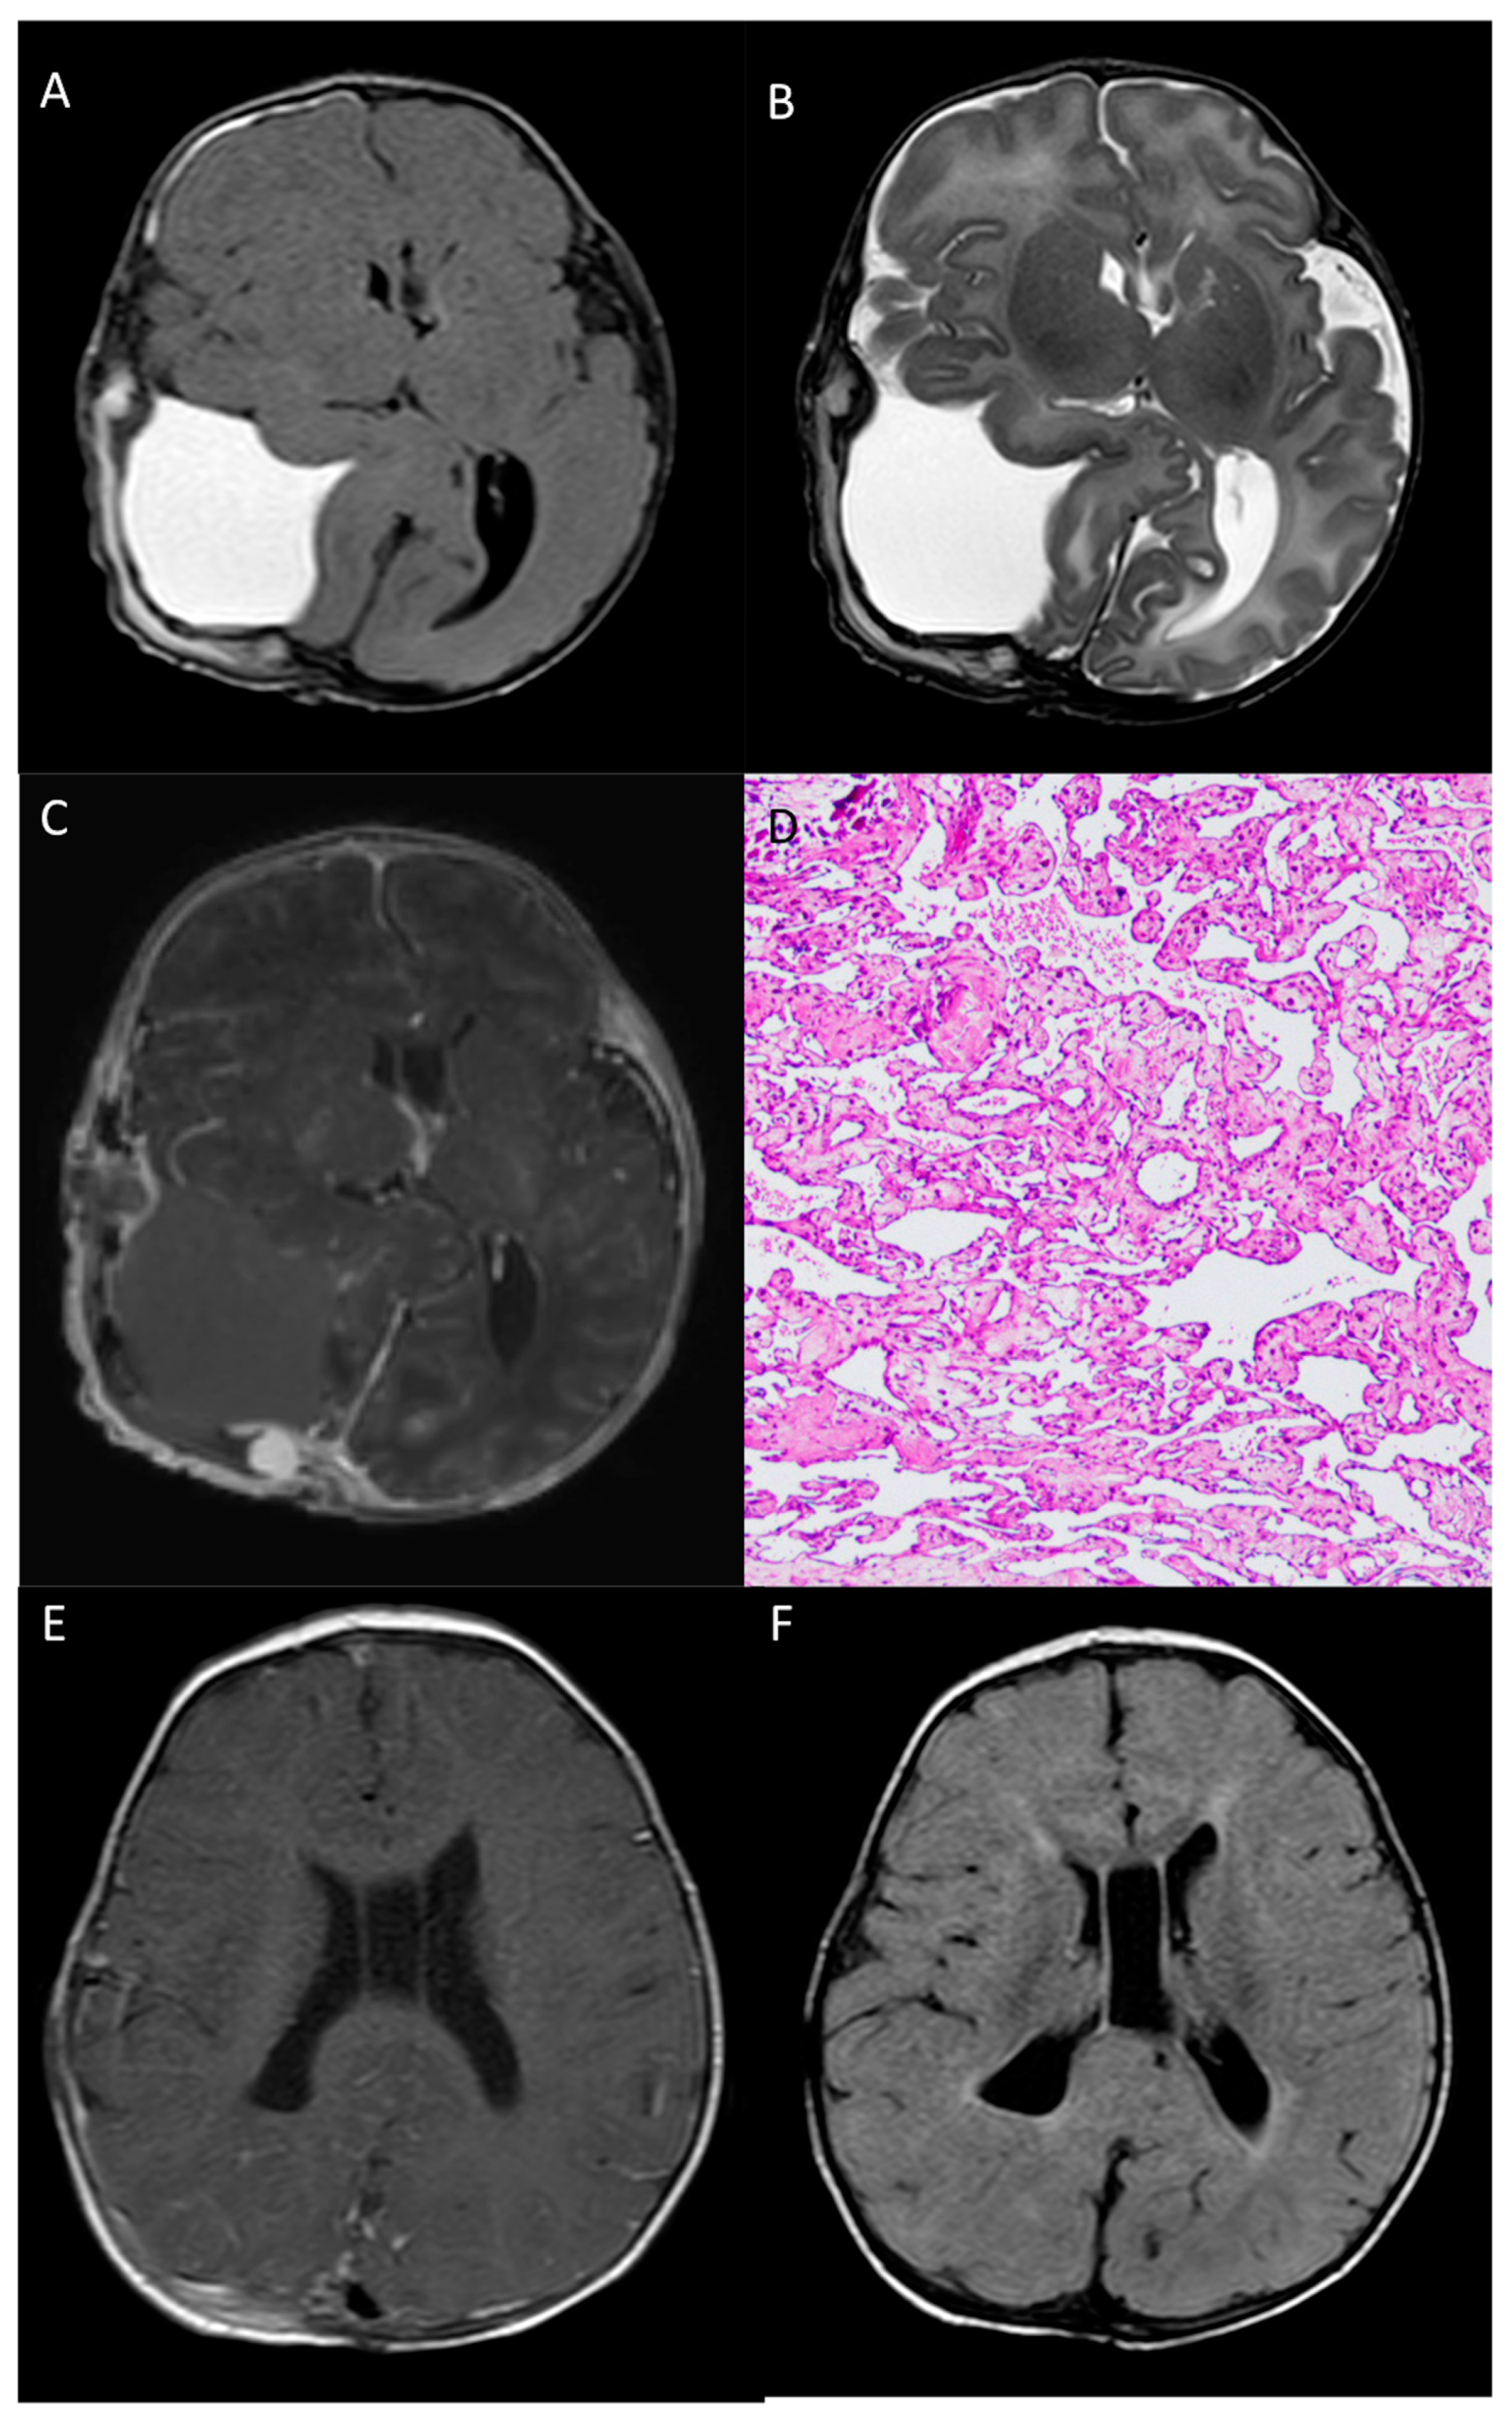

2.1. Presentation and Clinical Characteristics

2.2. Endovascular Embolization and Surgical Treatment